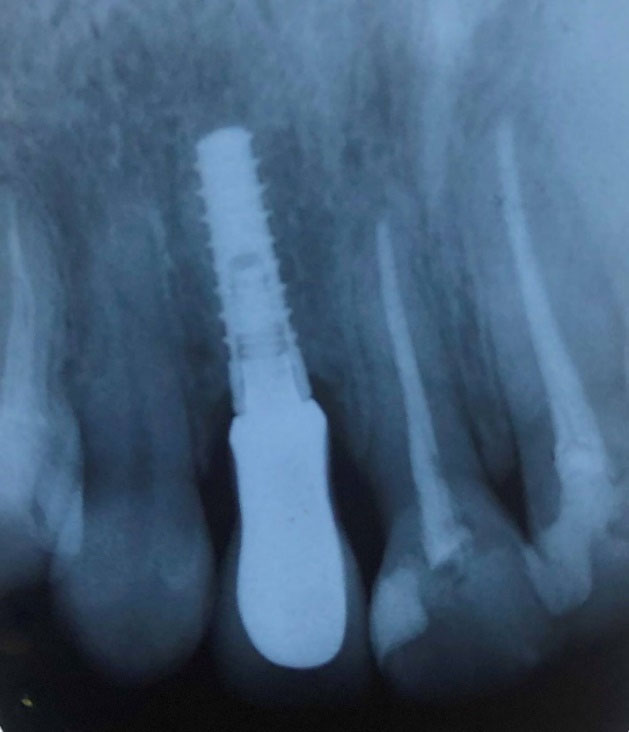

Figure 1.

Periapical view of the fresh socket implant at 12-month follow-up recall (a 24-year-old female, right maxillary lateral incisor).

The surgery was carried out under local anesthesia, using a minimally invasive technique. In cases with buccal bone fracture occurring during extraction, the whole implantation process was ceased, and the treatment plan was changed to delayed loading of the prosthesis or a GBR procedure. A periotome was used for cutting supra-crestal fibers, and the extraction of teeth was carried out using minimal buccolingual forces. Simultaneous extraction and implantation were carried out 2 mm apical to the buccal cortex at least and 2 mm lingual to the buccal table. This procedure was implemented by 35 N.cm2 torque at least (Figure 1).